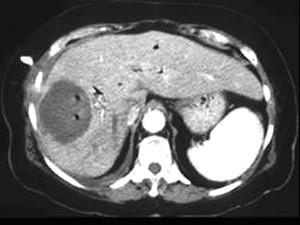

问题 男,48岁,寒战高热,右上腹痛一天,CT检查如图所示,最可能的诊断是 ( )

选项 A、肝错构瘤 B、肝转移瘤 C、肝脓肿 D、胆管细胞癌 E、原发性肝癌

答案 C